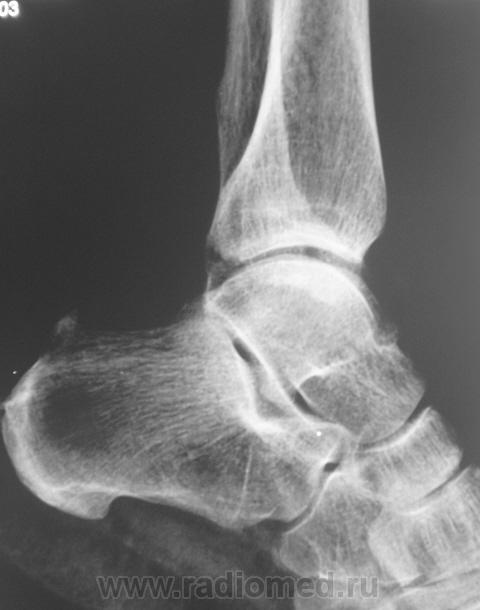

на консолидированный перелом Фолькмановского клина б\берцовой кости.

А, может быть, с учетом деформации малоберцовой кости, на боковой рентгенограмме, можно предположить, что, "это", откол фрагмента костной ткани от дистального эпифиза б/берцовой кости.

Если говорить о травме ( нужно учесть механизм), то можно предположить вдавленный перелом с огранич., но интенс. действием травмирующей силы с компрессией ( уплотнением) костной ткани.